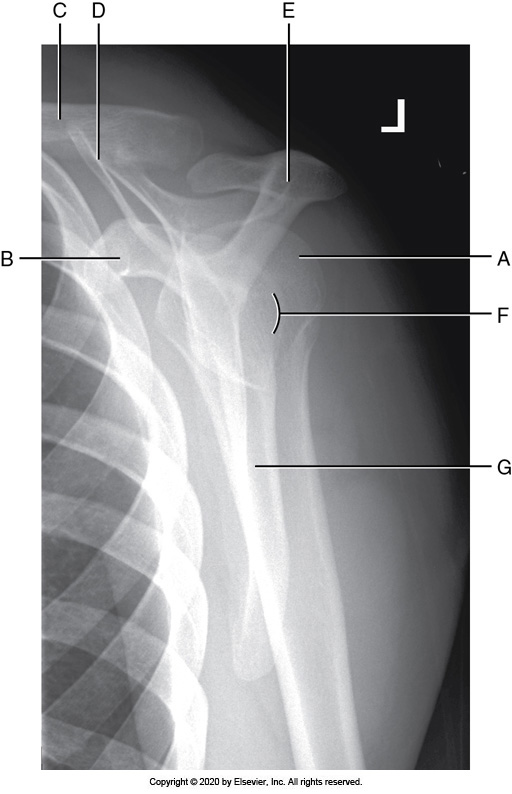

Identify the labeled "E" anatomy in the image below:

Lateral border